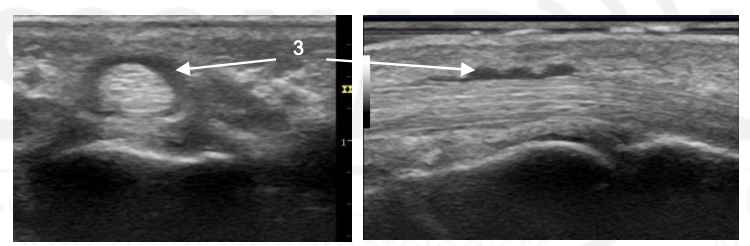

What is the arrow pointing to?

Synovial Distension